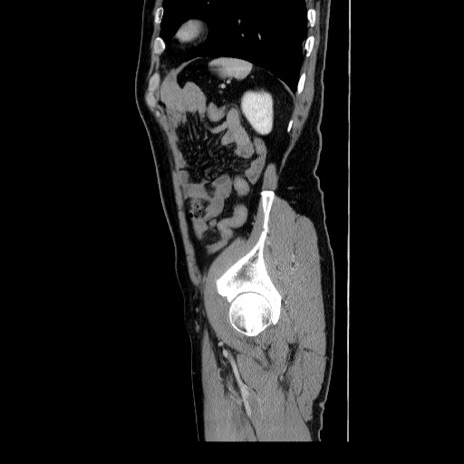

症例34(矢状断像)

【症例】60歳代 男性

【主訴】右鼠径部膨隆

【現病歴】1年程前より右鼠径部膨隆あり。自己にて還納可能だったため放置していた。3時間前より右鼠径部の脱出を認め、還納困難となり受診。

【身体所見】右鼠径部に小児頭大の膨隆あり。弾性硬であり、用手還納は困難。左鼠径部にも膨隆を認める。脱出はなし。